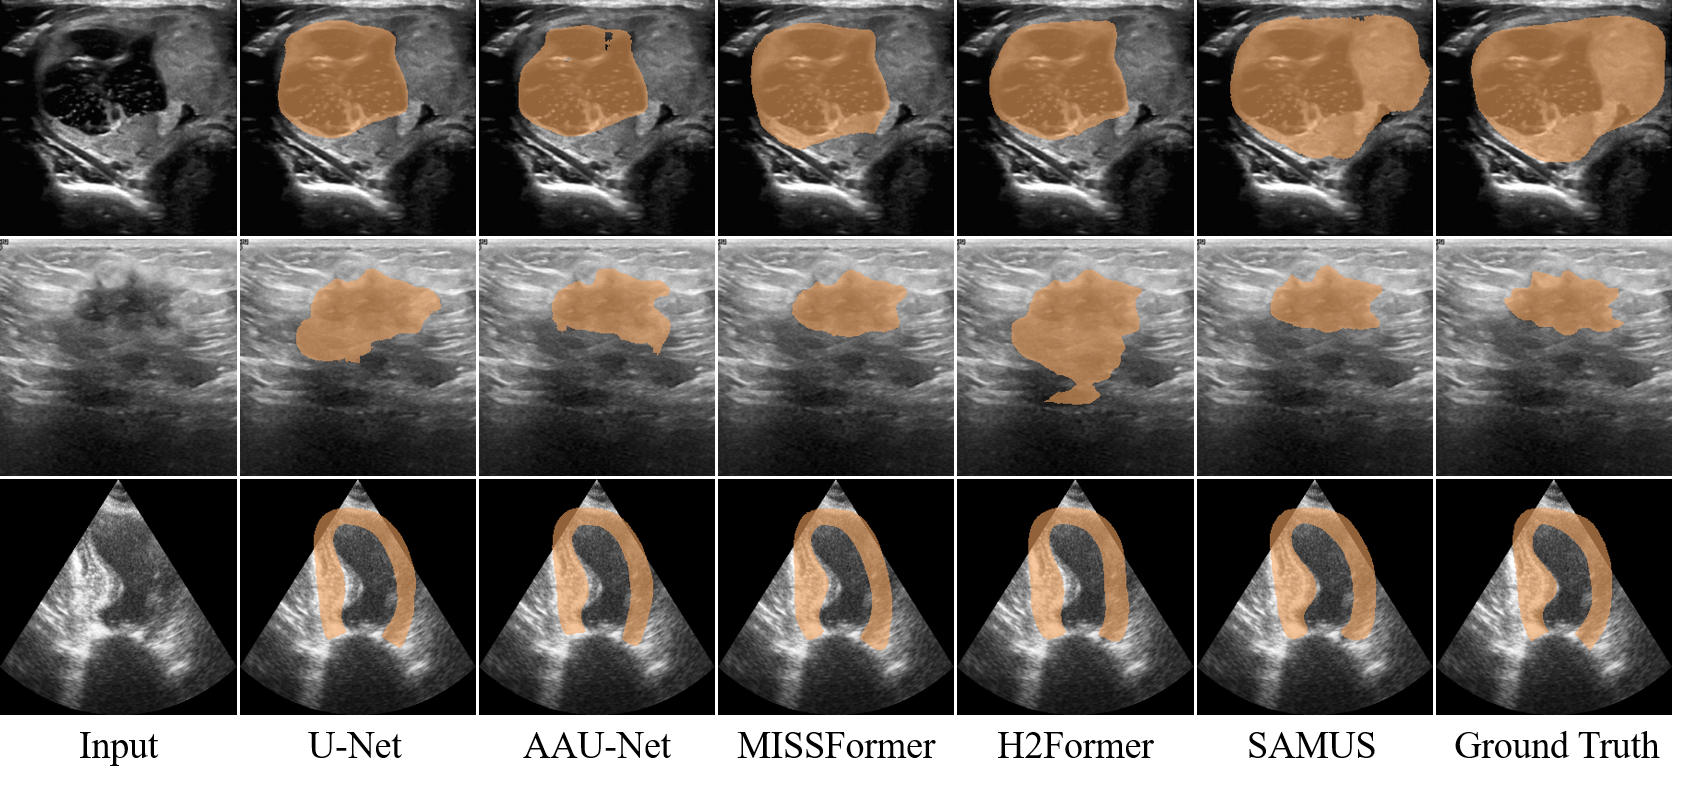

Qualitative results: Qualitative segmentation results of different methods, including U-Net (Ronneberger, Fischer, and Brox 2015), AAU-Net (Chen et al. 2022), MISSFormer (Huang et al. 2022), H2Former (He et al. 2023), and SAMUS, are illustrated in Fig. 4. Visually, segmenting the ultrasound images poses a challenge due to their low contrast, non-uniform features, and vague object boundaries. Existing methods struggle to accurately distinguish the target from the background, leading to extensive false negatives and/or false positives. Comparatively, SAMUS demonstrates superiority in preserving the integrity of target regions and reducing false positives. It is attributed to the inherent advantages of the SAM framework, as well as the specific adjustments and designs introduced in SAMUS.

Qualitative results: Qualitative segmentation results of different foundation models, including SAM, MedSAM, SAMed, MSA, and SAMUS, are presented in Fig. 5. Without tuning in medical images, SAM completely loses the ability to segment everything. Through applying tuning methods to SAM, MedSAM, SAMed, and MSA can somewhat restore the segmentation capability of SAM. However, they still struggle to accurately delineate segmentation boundaries in ultrasound images, resulting in extensive false negatives and false positives. In contrast, SAMUS exhibits superior performance by accurately locating segmentation boundaries, even for the low-contrast ones. It is consistent with the analysis that complementing local information with the image encoder is helpful, especially for boundary/shape preservation in medical image segmentation.